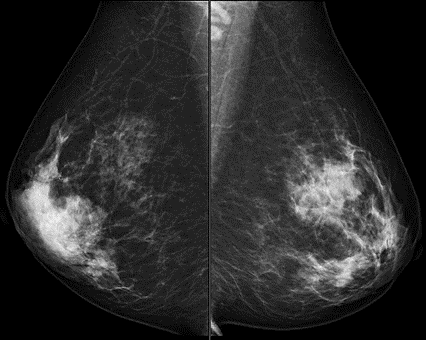

乳房撮影(マンモグラフィ)検査

乳房撮影装置 AMULET SOPHINITY

マンモグラフィ検査は乳房のX線検査です。樹脂の板で乳房を挟み乳房の厚みを最大限薄くし、乳腺を広げた状態で撮影をします。これは、乳腺に隠れた異常を見つけやすくするためです。この時、乳房には大きな力が加わるため患者様には強い痛みを感じる方がおられます。もし、とても強く痛みを感じ耐えられないようでしたら撮影にあたる放射線技師にお声がけください。

現装置には“なごむね”という機能を備えており、こちらは圧迫自動減圧機能となっております。乳房の厚みを変化させない範囲で圧迫圧を減圧し患者様の強い痛みを軽減させた状態で撮影を行うことができます。

また、現装置には旧装置になかったトモシンセシス(3Dマンモグラフィ)撮影が搭載されています。精査を目的として行う検査であり、角度を変えながら撮影をします。これにより従来の撮影では発見が難しかった病変の描出が可能となりました。

慣れない検査に緊張するとは思いますが、肩の力を抜いてリラックスしてお受けください。